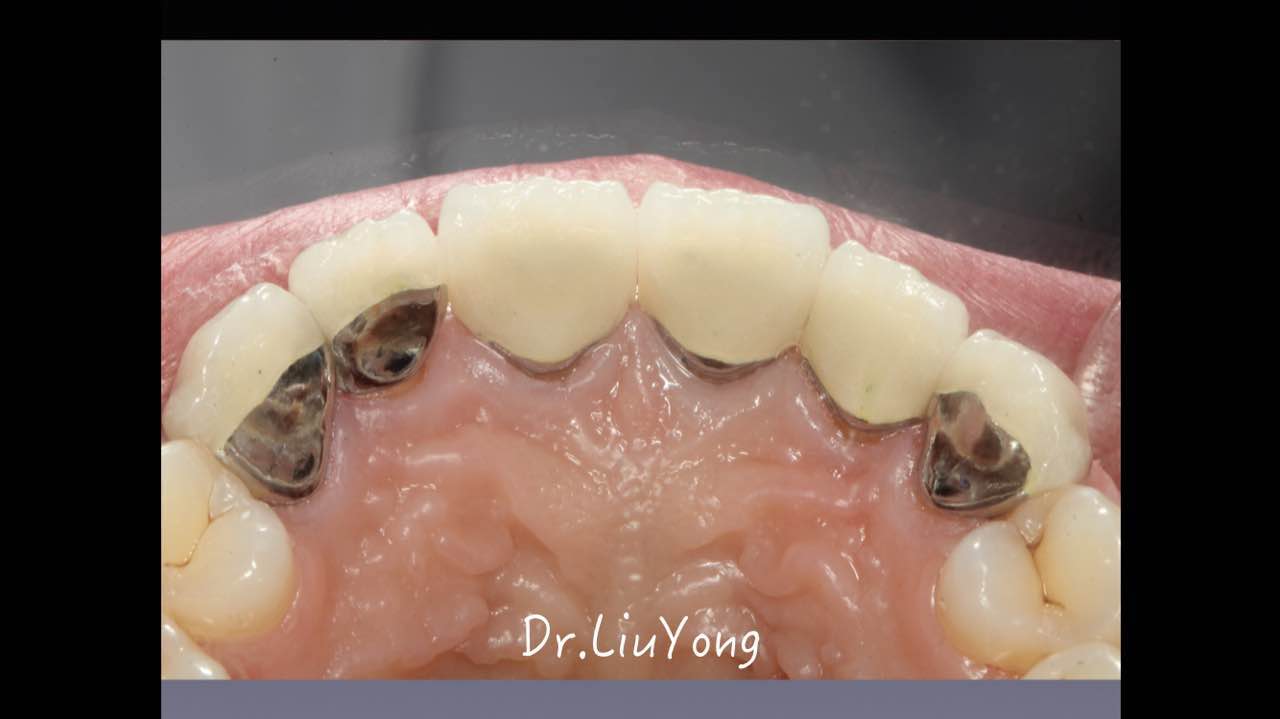

嚴重破壞生物學寬度,根尖瘺管,重行根管治療, 第一次冠延長建立唇腭側(cè)及鄰面BW,術后牙齦扇貝形差, 齦乳頭黑三角,再次行美學冠延長,建立牙齦扇貝形,手術免費, 患者因經(jīng)濟原因只能選擇鑄樁及鈷鉻合金烤瓷冠。終于完工